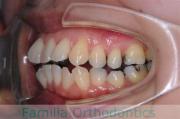

歯並びを治したいということで来院されました。下あごがやや右側に偏位して後退している、上顎前突(出っ歯)でした。上下左右から小臼歯を抜歯して、歯科矯正用アンカースクリューを併用したマルチブラケット法にて治療を行いました。約2年、24回の来院をしていただきました。

下顎の後退はいびきなどの上部気道の障害が出やすいと考えられます。